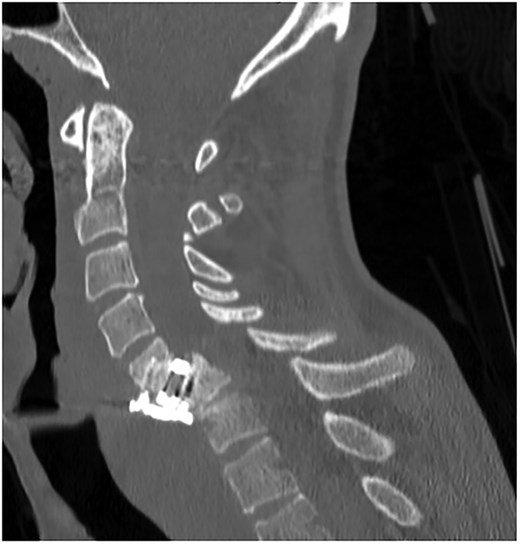

A 35-year-old male presented with a month-long history of dysphagia, severe headache, and posterior neck pain that radiated to the occiput. His medical history was significant for cervical surgeries, including an anterior cervical discectomy and fusion (ACDF) at C5/C6 one year and two months ago (Fig. 1). Shortly thereafter, the patient underwent revision surgery along with posterior plating from C5 to T1 due to osteomyelitis, worsening cervical deformity, and retropharyngeal abscess (Fig. 2). Initial workup included a noncontract computed tomography (CT), demonstrating increased gas density at C6 corpectomy site and post cricoid region (Fig. 3). A swallow study was obtained based on suspicion of a perforation and demonstrated extraluminal leakage of contrast posteriorly at the C6 level, consistent with initial CT (Fig. 4). Surgery included removal of the anterior and posterior hardware and esophageal repair. Although initially the esophageal injury was suspected to be related to the hardware, intraoperatively, it was found the instrumentation was not in communication with the esophagus. This confirmed the perforation was unrelated to direct injury from the cervical hardware construct, which was intact. The esophagus was repaired with a pectoralis flap. The postoperative course was uneventful, and the patient was discharged home after one week. The patient later died due to severe complications of substance abuse unrelated to the operation.

Sagittal T2-weighted MR of prior retropharyngeal abscess that led to revision and posterior plating from C5 to T1.